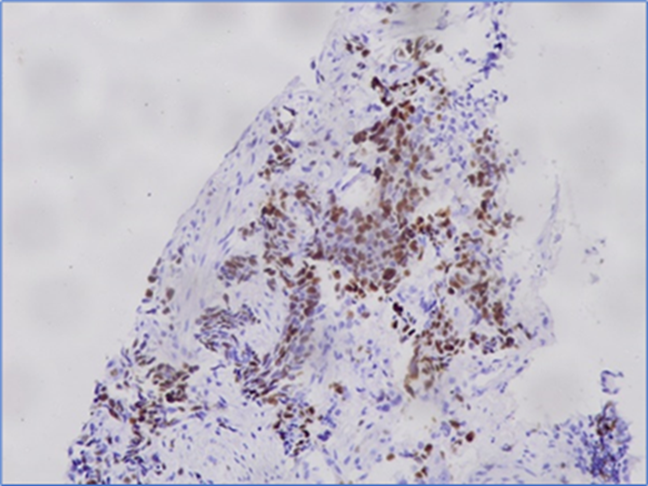

Expressions of Ki-67 and E-cadherin are given in FIGURE 1 and FIGURE 2, respectively. Of the 25 NSCLC tissue samples, 15 exhibited positive expression for E-cadherin, while 15 were negative for Ki-67 expression. Of the 15 NSCLC tissues with positive E-cadherin expression, Ki-67 was positive in 6 cases. Conversely, among the 10 NSCLC tissues negative for E-cadherin, Ki-67 was positive in 4 cases. However, no statistically significant association (P=0.99) was identified between Ki-67 and E-cadherin expression (TABLE 1). No statistically significant association was found in the expressions of both Ki-67 and E-cadherin with age, sex, family history of lung cancer, histological type, tumor differentiation, and lymph node metastasis except E-cadherin expression and co-morbidity of the patients (P=0.01).

FIGURE 2 Expression of E-cadherin in non-small cell lung cancer tissue